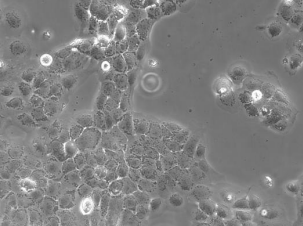

CaSki(人宫颈癌肠转移细胞)

CaSki细胞是从小肠肠系膜转移灶的细胞中建立的。据报道,CaSki细胞含有完整的HPV-16(每个细胞大约600个拷贝)和HPV-18相关序列。

细胞形态

上皮细胞样

细胞类型

肿瘤细胞

生长特性

贴壁细胞